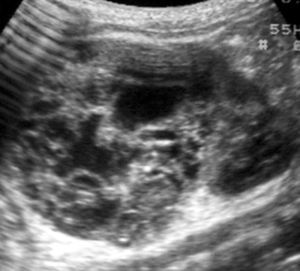

Los pacientes con diagnóstico histológico de tumor quístico multilocular (n = 7) tenían entre 5 meses y 12 años, siendo 4 de ellos varones y 3 mujeres. La clínica inicial fue la de masa abdominal palpable en 5, hematuria en uno y dolor abdominal en el paciente mayor. Se identificaron masas renales bien definidas que presentaban un aspecto quístico, con múltiples loculaciones separadas por septos que mostraban discreto realce (figs. 3 y 4). En un paciente se encontraron focos de blastema en las paredes de los septos en el estudio histológico.

Fig. 3. Tumor quístico multilocular. (A) Ecografía abdominal. Corte renal longitudinal. Masa renal heterogénea con predominio de áreas anecoicas. (B) Tomografía computarizada abdominal con contraste intravenoso. Corte sobre polo superior renal izquierdo. Masa de aspecto multiquístico que presenta zonas de parénquima renal sano entre las formaciones quísticas.